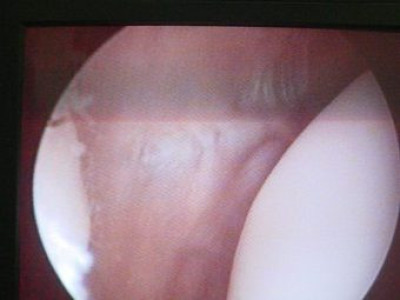

Luxación Habitual de Rótula

Envíado por Dr. Eduardo E. Martínez Melara